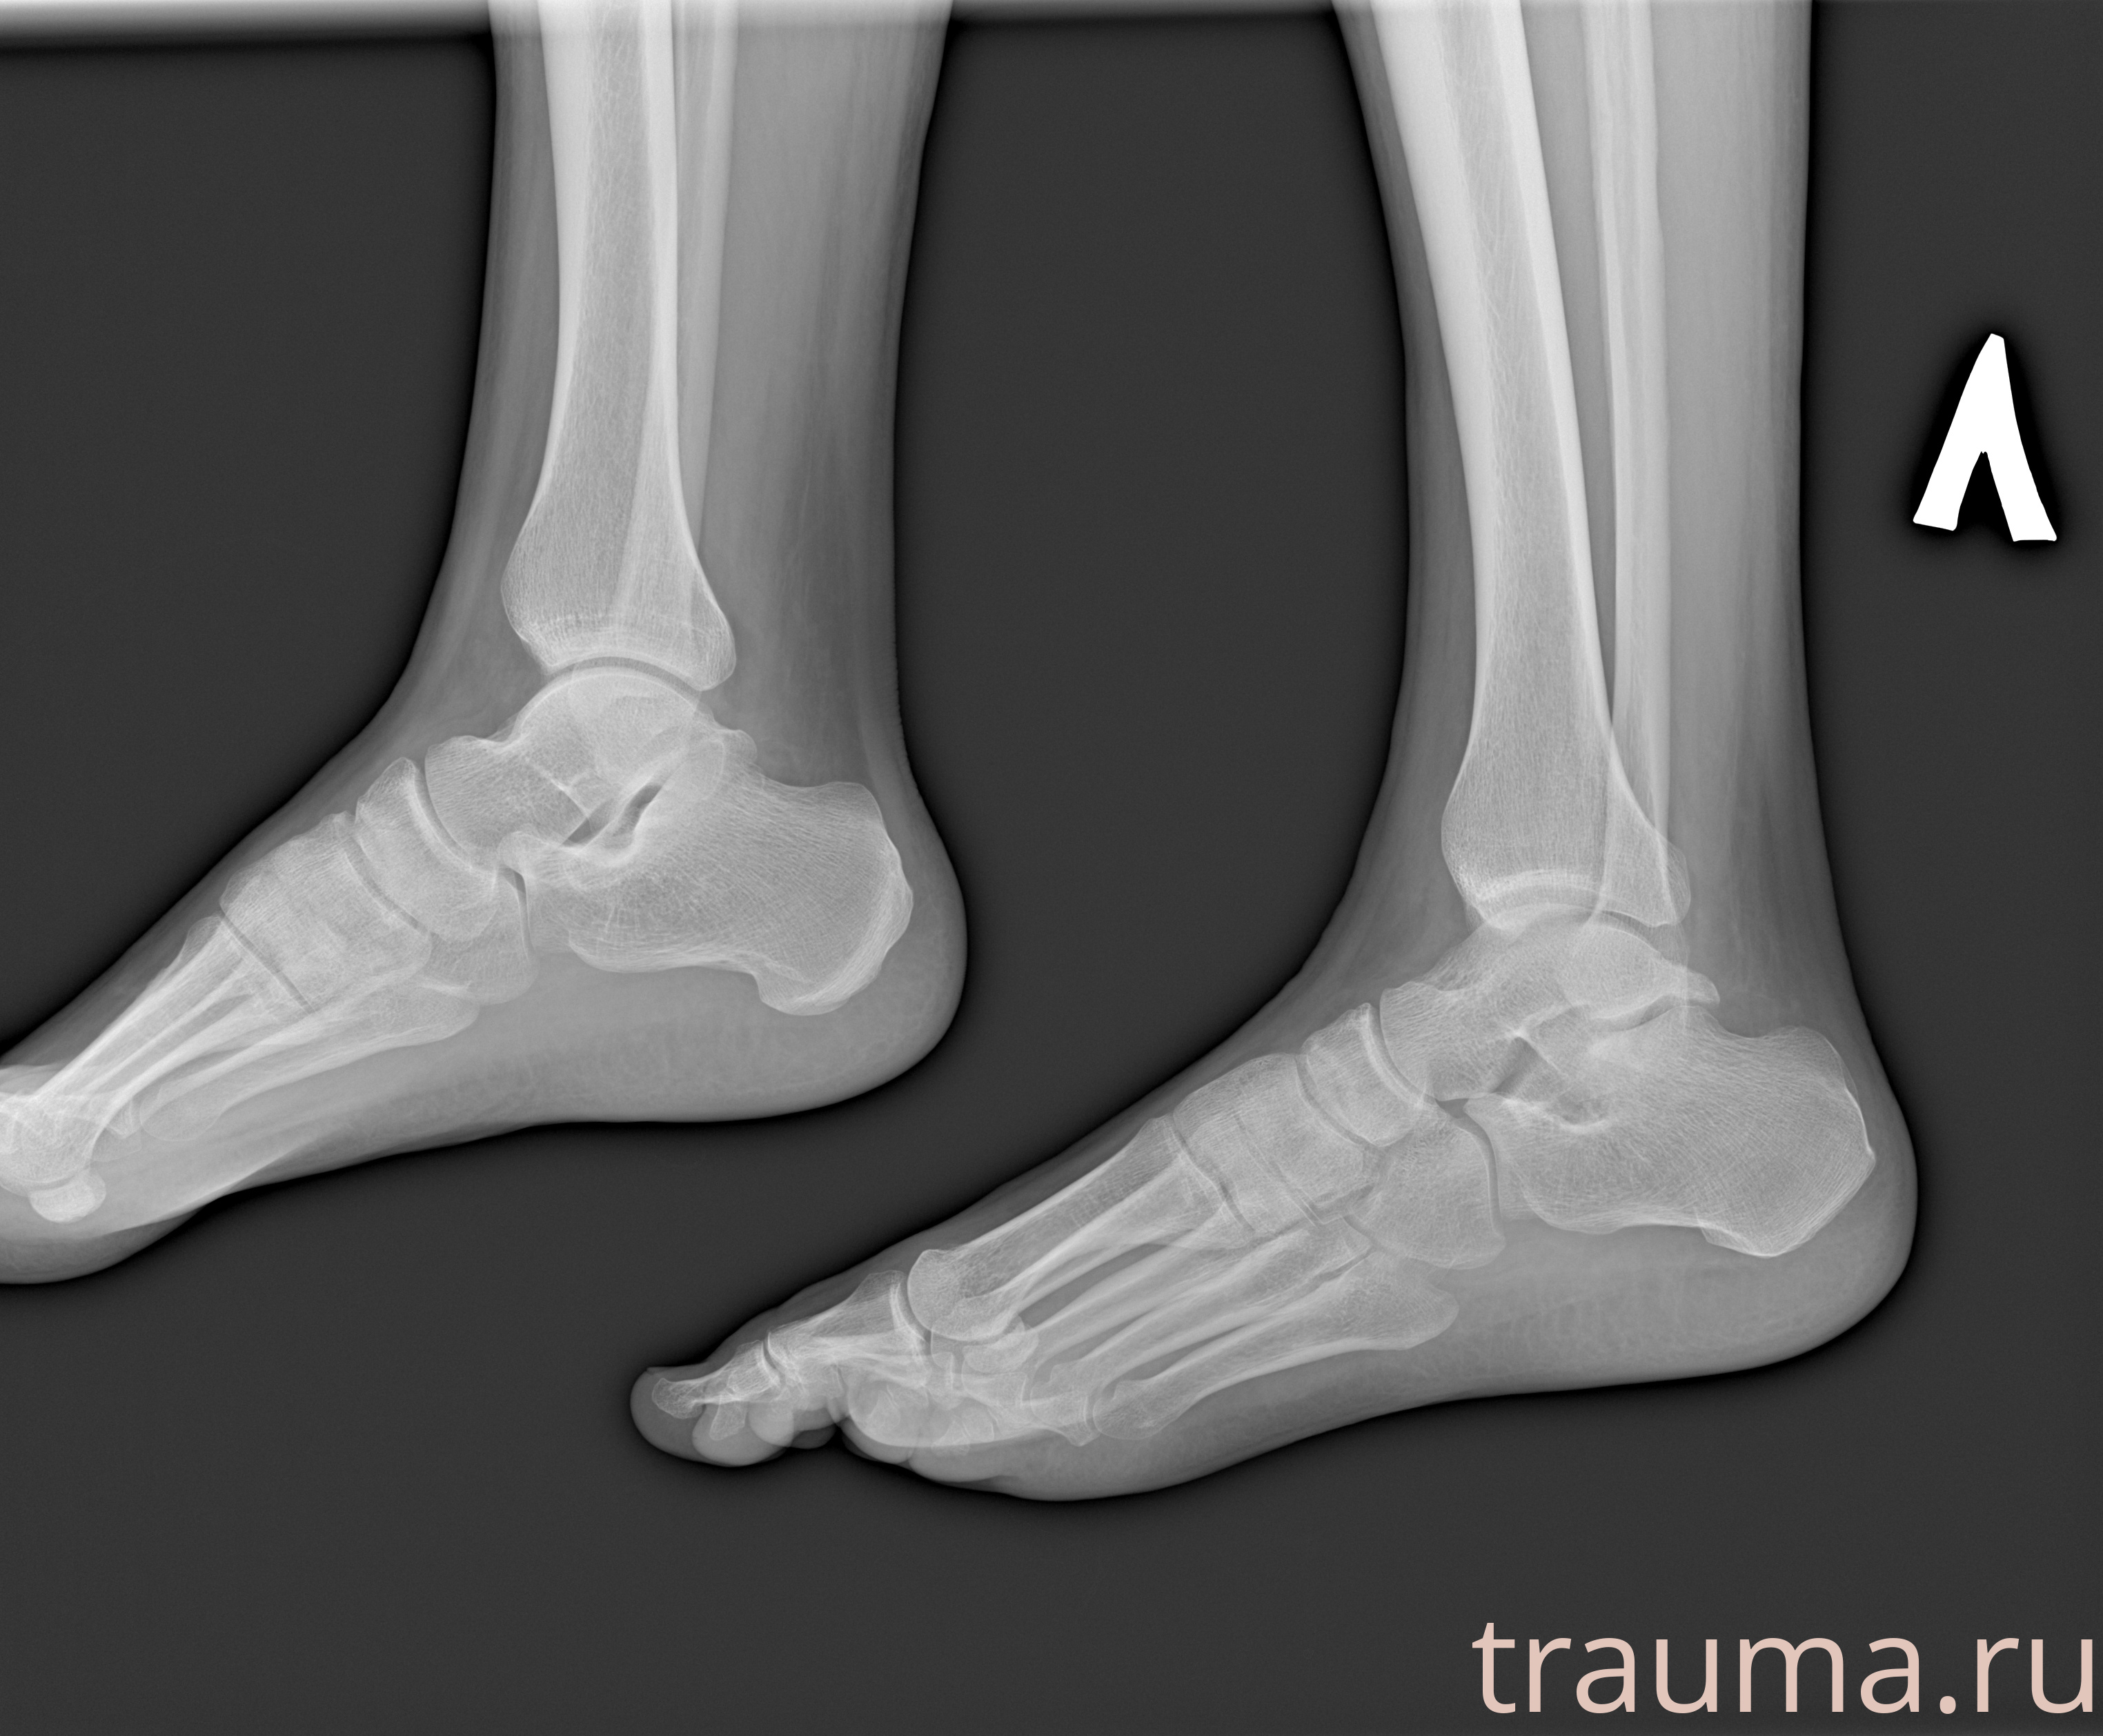

Рентгенограммы

Рентген на дому: по вашему адресу приезжает врач-рентгенолог, травматолог-ортопед с мобильным рентгеновским аппаратом, проводит диагностику травмы или заболевания, делает необходимые рентгенограммы, дает рекомендации по дальнейшему лечению. Получить качественные снимки в домашних условиях возможно благодаря уникальной методике, разработанной МосРентген Центром для института  Склифосовского